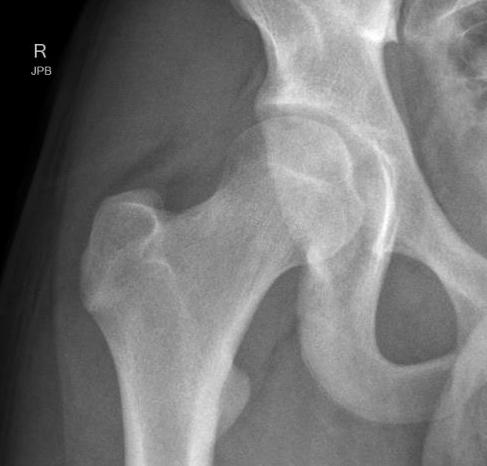

ASIS Avulsion

Attachments

Sartorius & Tensor fascia lata

Imaging

ASIS displaced 1ASIS displaced 2